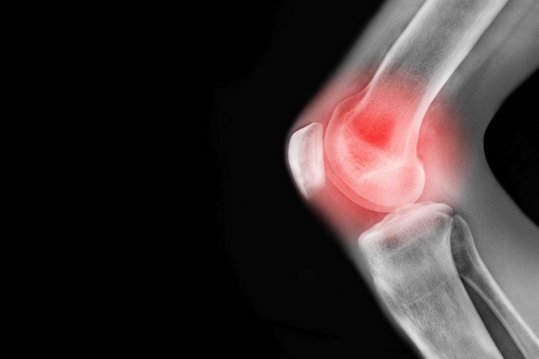

很多人都饱受关节炎疼痛之苦,特别是一些风湿性关节炎患者,常年风,老不好,一到下雨天就感觉关节痛疼难忍,长此以往,关节逐渐变形等等。为什么很多人寻遍了名医,吃了很多药却总是未能治好关节病?这跟平时的饮食习惯有很大的关系。专家指出,治疗关节的炎,不要盲目,要吃对食物,避免更严重。

关节炎泛指发生在人体关节及其周围组织的炎性疾病,可分为数十种。我国的关节炎患者有1亿以上,且人数在不断增加。临床表现为关节的红、肿、热、痛、功能障碍及关节畸形,严重者导致关节残疾、影响患者生活质量。关节炎的病因复杂,主要与炎症、自身免疫反应、感染、代谢紊乱、创伤、退行性病变等因素有关。其突出的临床表现为:反复发作的、对称性的、多发性小关节炎,以手部指掌、腕、足趾等关节最常见。 专家说到,早期呈现红、肿、热、痛和功能障碍,晚期关节可出现不同程度的强硬和畸形,并有骨和骨骼肌萎缩,是一种致残率较高的疾病。